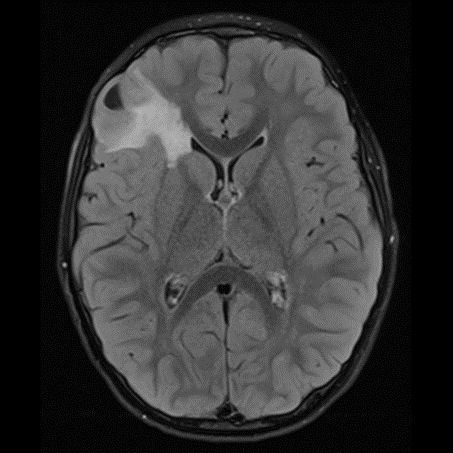

DNET:Özellikle erkek çocuk ve nöbet öyküsüyle gelen hasta kortikal yerleşim ve t1 ağırlıklı serilerde hipointens t2a ve flair serilerde ise hiperintens görülmesi bu tanıma uymaktadır. Hastaların 5’te birinde frontal lobda da tutulum olabilir. Lezyon çevresinde ödem ya da içerisinde kalsifik odak izlenmemiştir:

DNET:Özellikle erkek çocuk ve nöbet öyküsüyle gelen hasta kortikal yerleşim ve t1 ağırlıklı serilerde hipointens t2a ve flair serilerde ise hiperintens görülmesi bu tanıma uymaktadır. Hastaların 5’te birinde frontal lobda da tutulum olabilir. Lezyon çevresinde ödem ya da içerisinde kalsifik odak izlenmemiştir.